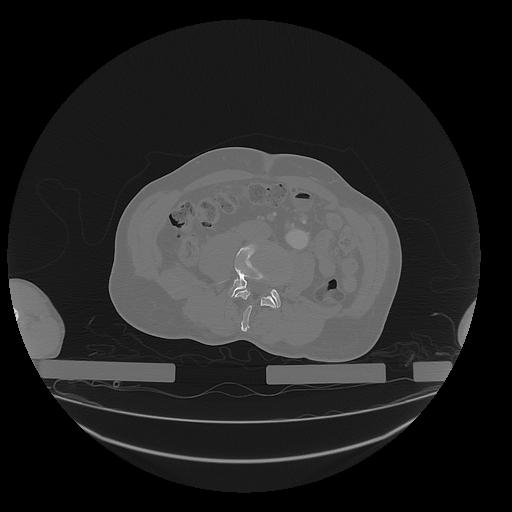

31 PULMON,CE,Vol,1.0,PULMON,,